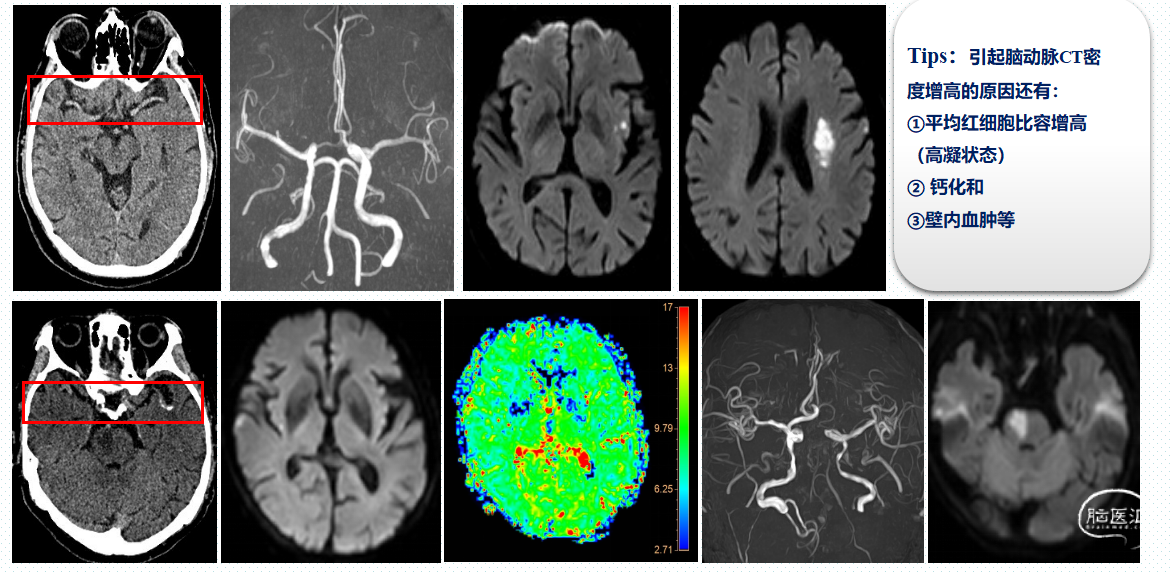

(二)、影像评估---组织窗评估:

MRI表现:DWI代表核心梗死区,对急性期病灶检出具有明显优势:① 在发病35min-6h内DWI即可发现高信号;② 后循环敏感,对脑干梗塞、小脑梗塞较CT更全面。

DWI影像改变:

超急性期(6h内)梗死区局部细胞毒性水肿,T2WI没有异常,DWI呈高信号,ADC呈低信号。

急性期(24h)细胞毒性水肿逐步向血管源性水肿转变,T2WI信号开始升高,DWI仍呈高信号,ADC呈低信号

亚急性期(7d)水肿进一步加重,T2WI上呈高信号,DWI仍呈高信号,ADC图上低信号逐渐上升。

慢性期(30d)脑组织坏死,T2WI和ADC图呈明显高信号,弥散不受限。

脑卒中急性期DWI、T2、ADC的影像表现如下:

根据发病3小时内或4.5小时内时间窗CT评估后进行评估溶栓外,对醒后卒中或超4.5小时时间窗的患者,在具备CT和核磁共振设备的医院可进行组织窗评估,对醒后卒中从睡眠中点至入院在9小时内的患者经组织窗评估存在错配:即CT无病灶,DWI有病灶而FLAIR无明显改变,说明在4.5小时时间窗内,明确责任病灶,仍然可积极进行静脉溶栓。

组织窗评估——DWI-FLAIR 错配:

存在 DWI-FLAIR 错配定义:DWI 显示高信号,FLAIR 信号改变不明显区域.

DWI-FLAIR 错配表明组织缺血时间在 4.5 小时内,可以作为静脉溶栓筛选指标,适用于醒后脑卒中患者进行溶栓决策。

不存在 DWI-FLAIR 错配:

DWI和FLAIR上相应区域均可见明显高信号 。适用于醒后或超时间窗脑卒中患者评估,不存在 DWI-FLAIR 错配说明不能进行静脉溶栓,溶栓获益较小而且出血风险增加。

DWI和FLAIR与MRA的影像评估:

明确责任血管和责任病灶,为静脉溶栓和血管内介入治疗提供决策依据。

组织窗评估—DWI-PWI 错配

核心梗死区:ADC 值<600 秒/mm2的 DWI 高信号区域。

低灌注区:Tmax>6 秒,或 rMTT 值>145%对侧正常脑组织。